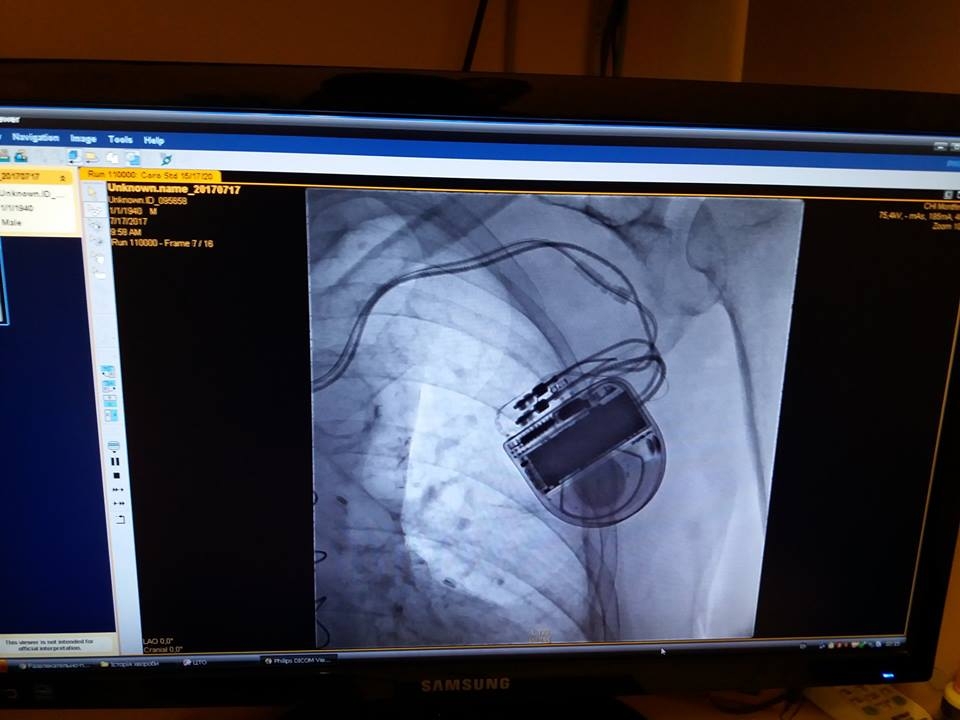

Система КД

складається з електрода або електродів (в залежності від модифікації), які заводяться

та фіксуються в серці людини, та безпосередньо приладу, який розміщується під

шкірою в грудній ділянці і до якого під’єднані вище вказані електроди. Функції